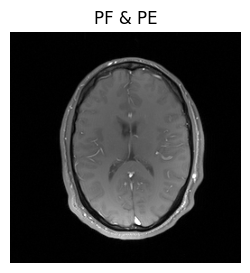

show_images(magnitude_fully_sampled, magnitude_pe_pf, titles=['fully sampled', 'PF & PE'])

Well, we got an image, but when we compare it to the previous result, it seems like the head has shrunk. Since that’s extremely unlikely, there’s probably a mistake in our reconstruction.